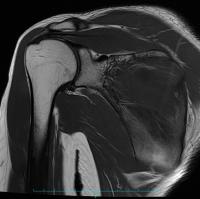

肩関節